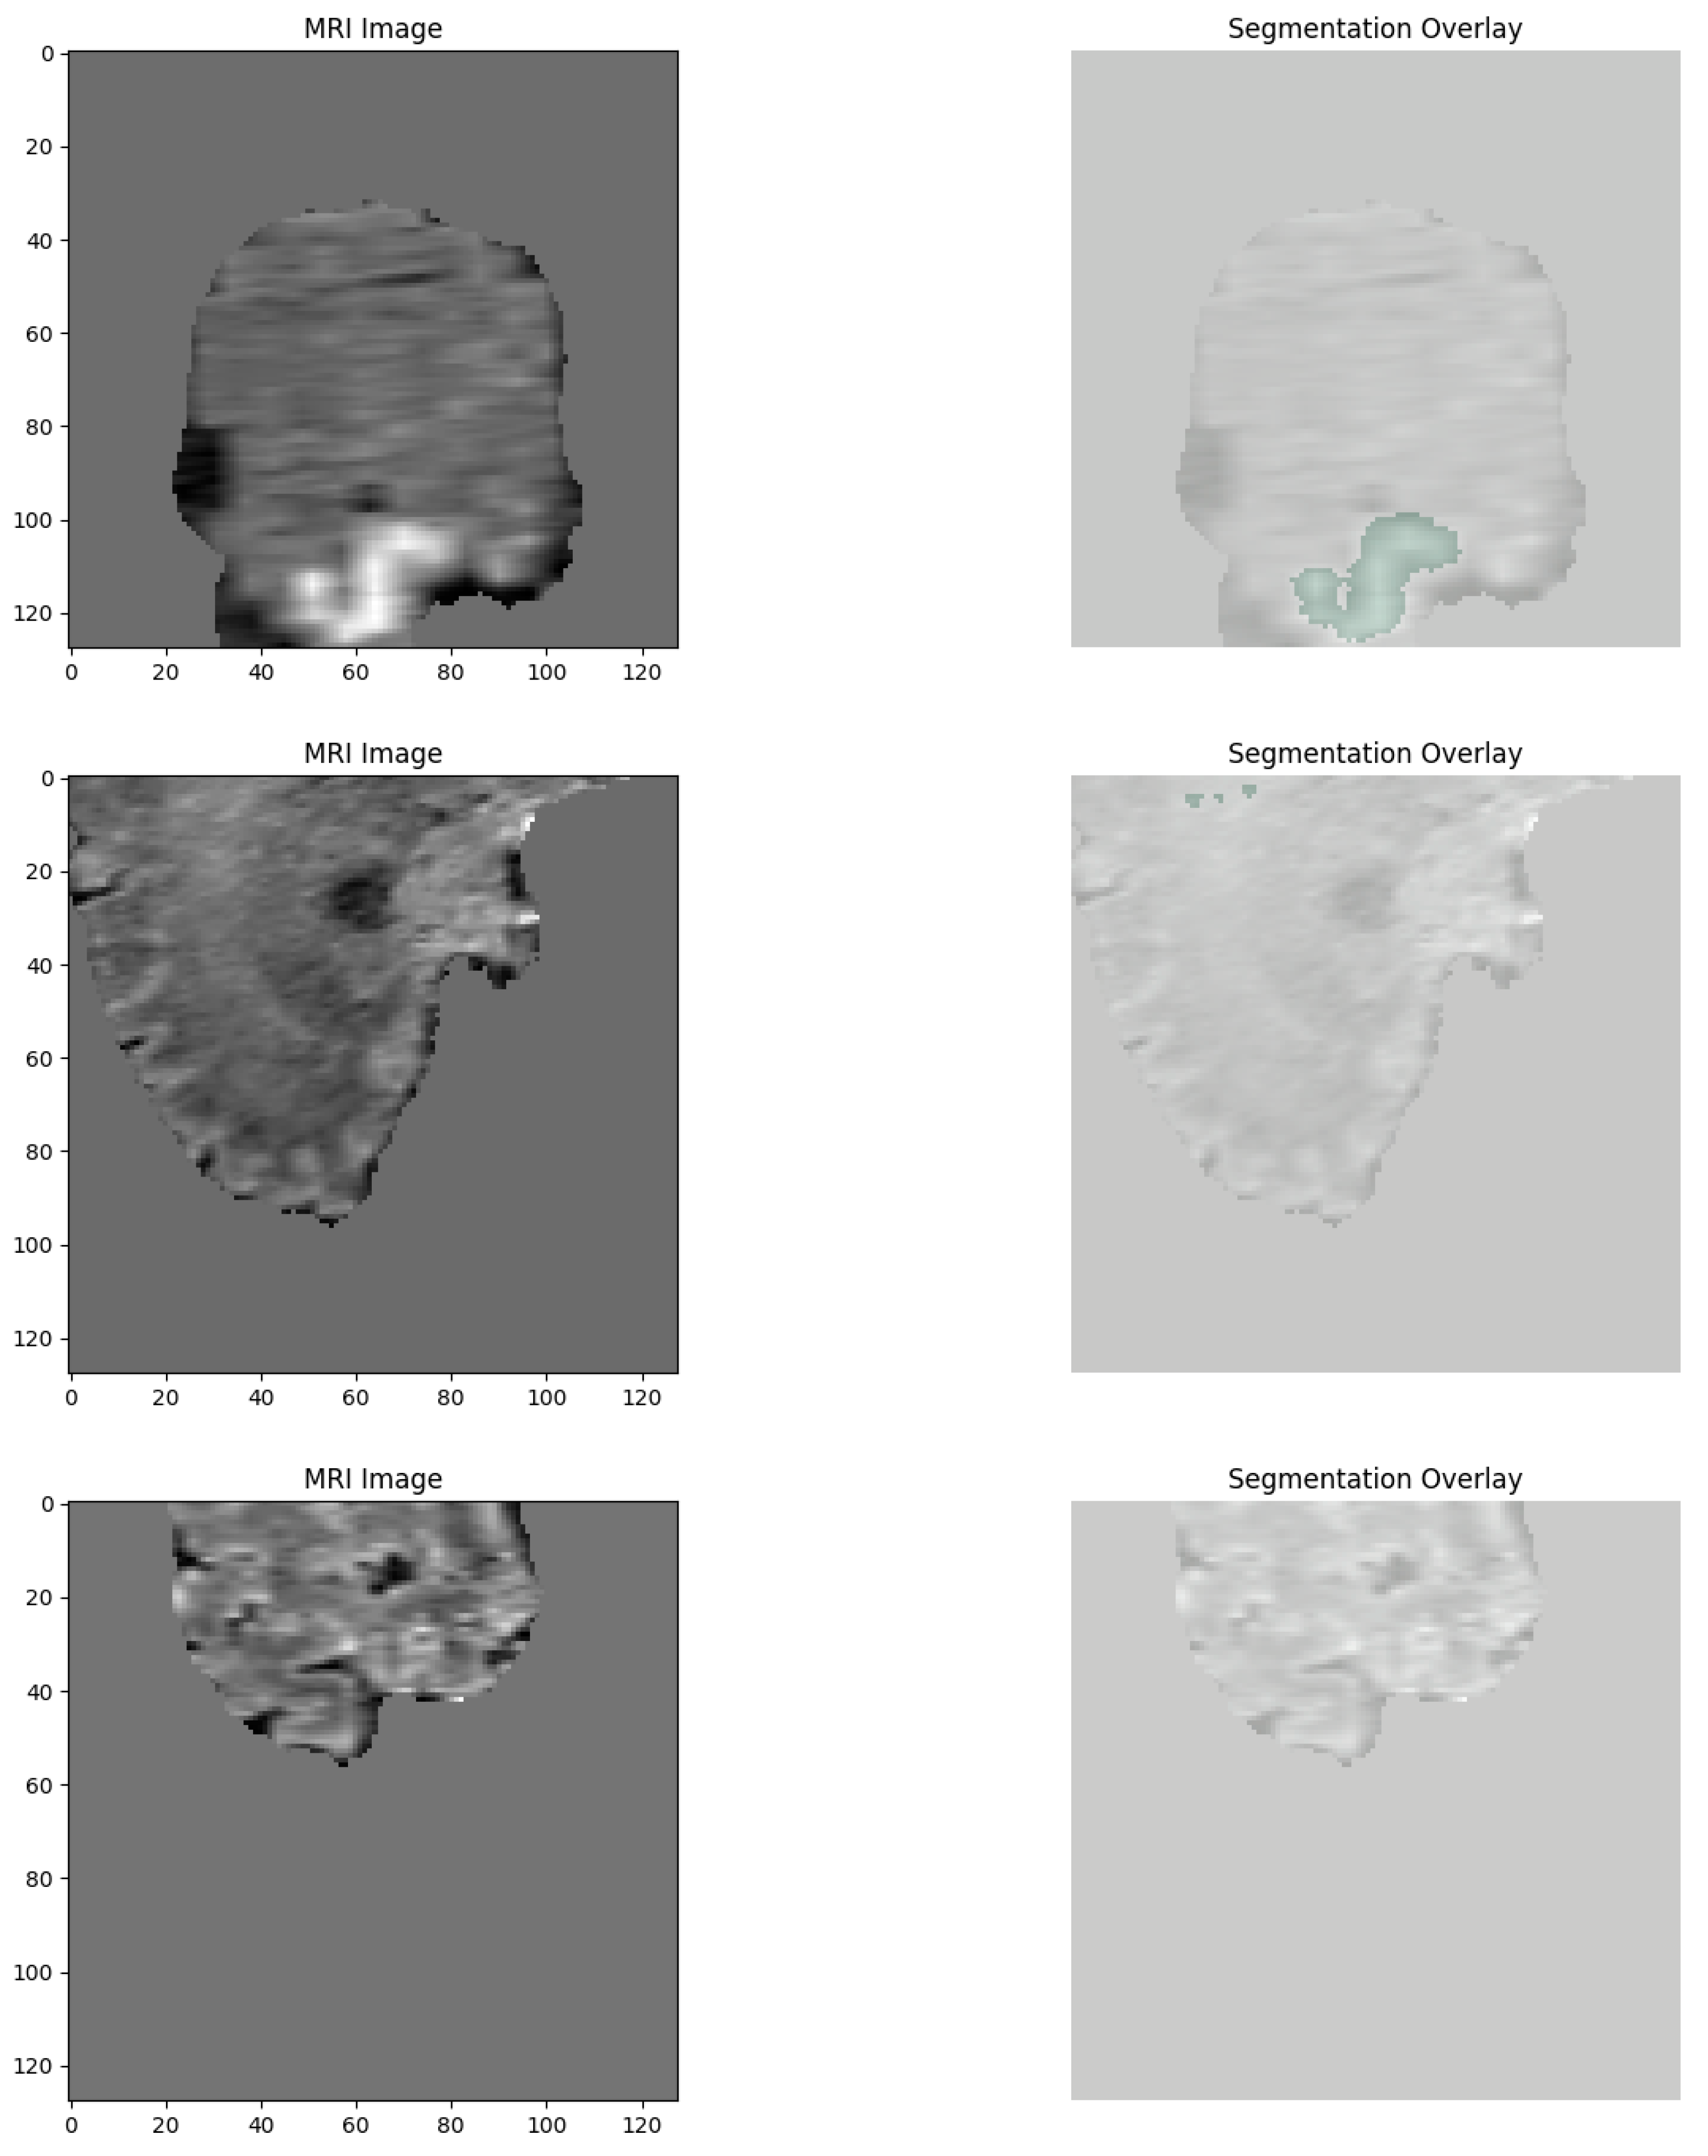

The two independent but complementary brain tumor datasets from MRI scans were utilized in this study for the classification and segmentation tasks, respectively. The first dataset was utilized for the task of 2D classification of the type of tumor, while the second one was utilized for 3D segmentation of the tumor. Both datasets were subjected to intensive preprocessing routines designed to make them as amenable as possible to deep learning-based modeling. For the tumor type classification task, we retrieved data from a merged and curated repository of two publicly available sources. The first source was the Kaggle Brain Tumor MRI dataset, comprising labeled 2D MRI slices representing four tumor classes: glioma, meningioma, pituitary tumor, and no tumor. The second source was the SciDB Brain Tumor dataset, from which we used additional segmentation annotations that were integrated during preprocessing. The combined dataset derived from the union of several sources greatly added to diversity and overall image quality, in addition to ensuring there was a good balance of tumors throughout the whole set (Figure 1).

Figure 1. Random samples from each class in the 2d classification dataset.